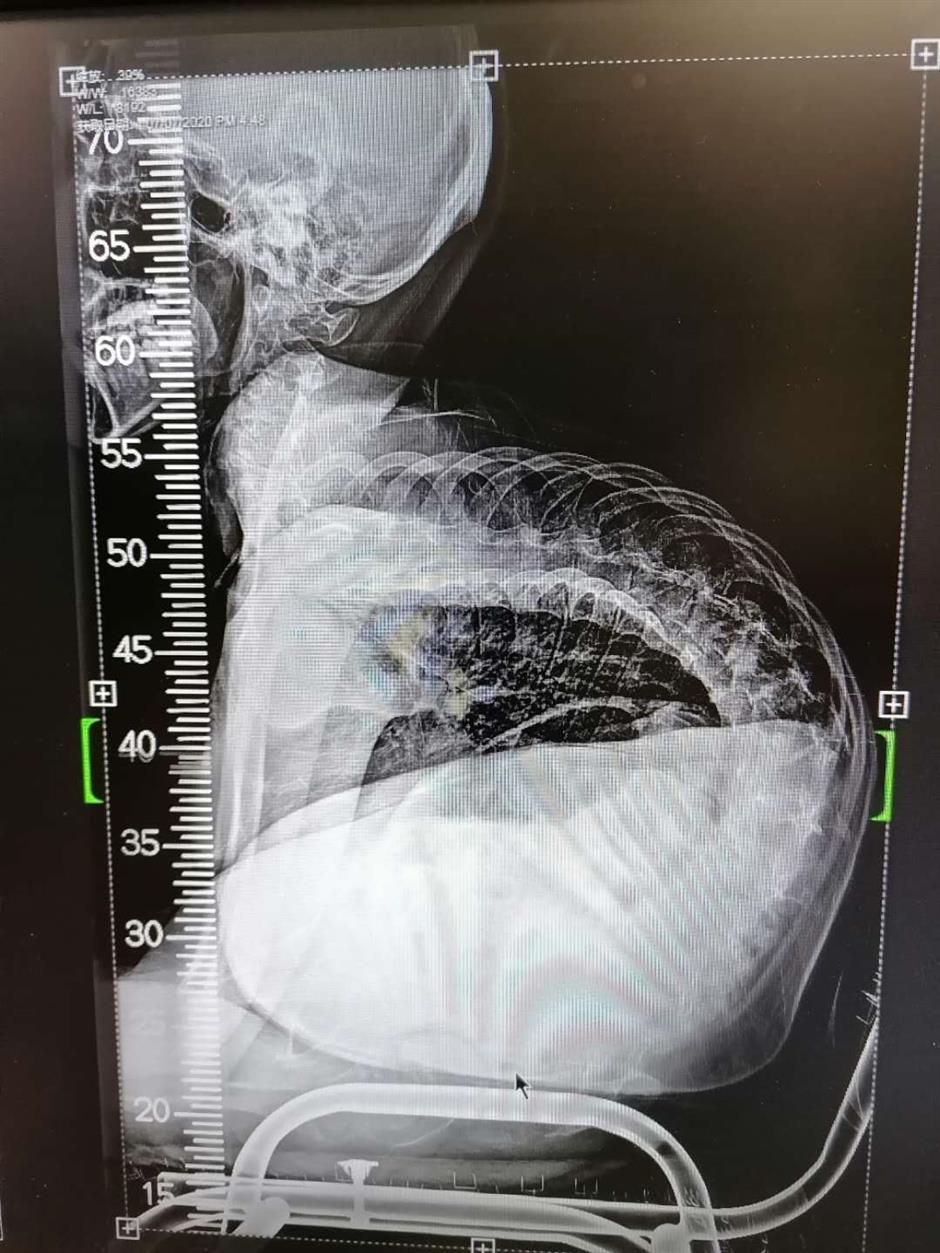

From www.shine.cn

Surgery straightens boy's severely curved spine SHINE News Is There A Way To Fix A Curved Spine There are three main types of spine curvature disorders, including: Focus on mobility to loosen up the back. The exercises will help you attain and maintain a better spinal. Also called swayback, the spine of a person with. The way to deal with your scoliosis depends on how severe the curve of your back is. Used in combination, they hold. Is There A Way To Fix A Curved Spine.